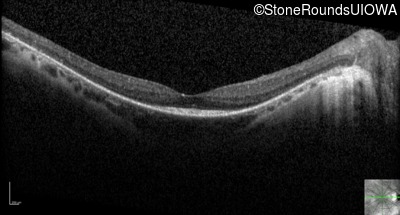

Optical Coherence Tomography - Left - 20/20 -2

Exemplar / OCT Stack